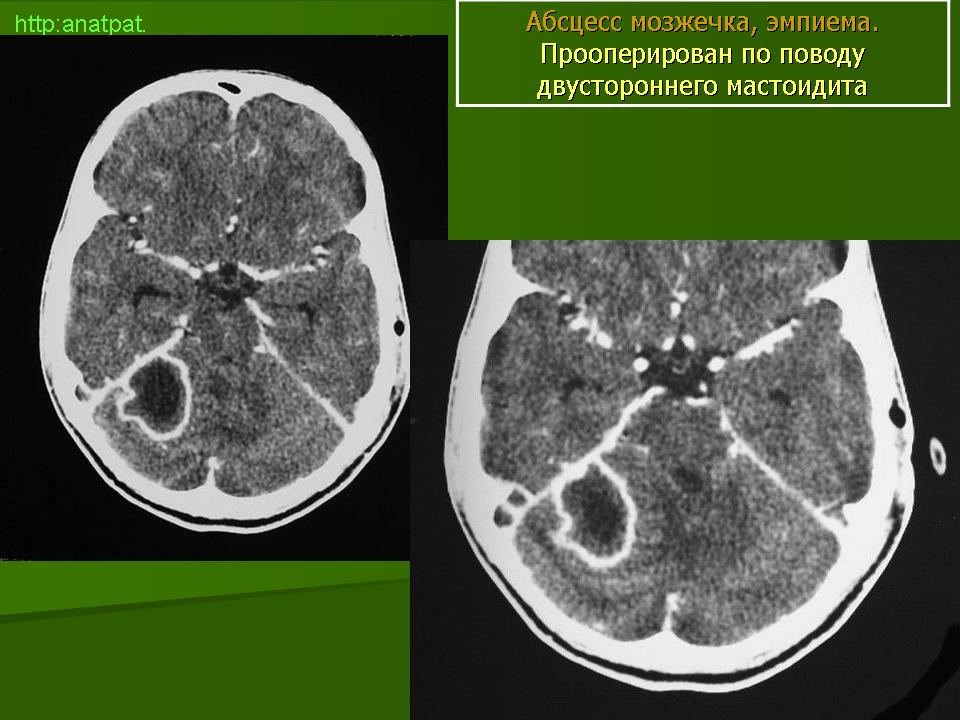

Абсцесс головного мозга – это очаговое скопление гноя в мозговом веществе, окруженное капсулой.

Абсцессы могут локализоваться в различных участках мозгового вещества. Обычно абсцессы сочетаются с менингоэнцефалитами, энцефалитами, сопровождаются повышением температуры тела, воспалительными изменениями крови и ликвора. Клиническая картина разнообразна и состоит из различных сочетаний общемозговых симптомов (головной боли, головокружения, тошноты, рвоты, нарушений сознания), менингеальной (оболочечной) и очаговой неврологической симптоматики.

Компьютерная (КТ) или магнитно-резонансная (МРТ) томография головного мозга являются ведущими методами диагностики посттравматических абсцессов, позволяющих судить об их расположении, объеме, структуре, консистенции, содержимом, воздействии на вещество головного мозга. Для исключения опухолей головного мозга, туберкулом, паразитарных заболеваний проводится ОФЭКТ (однофотонная эмиссионная компьютерная томография).